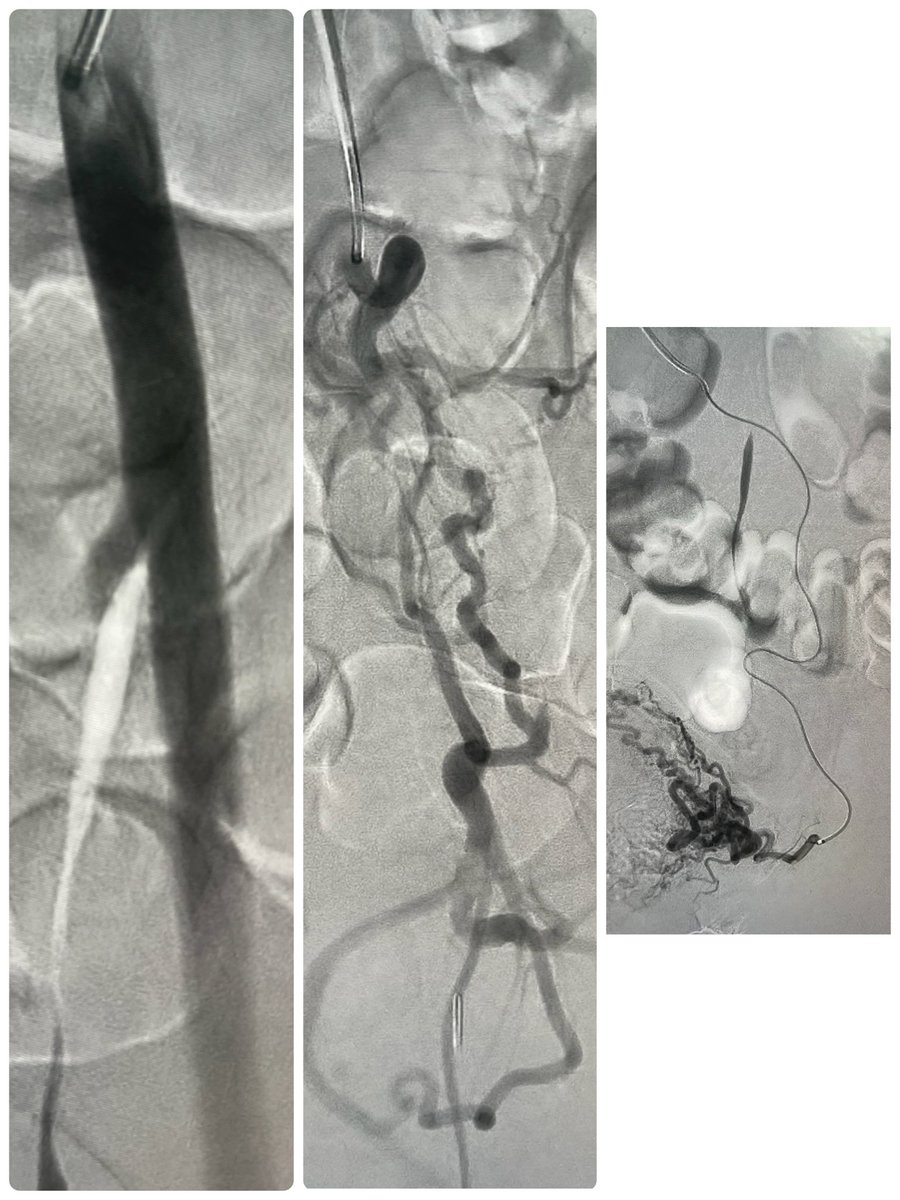

Central veins occlusion! Symptomatic pt. Irad Eshel can help to open the veins “. كذلك فتح اورده الصدر المقفله المزمنه باذن الله